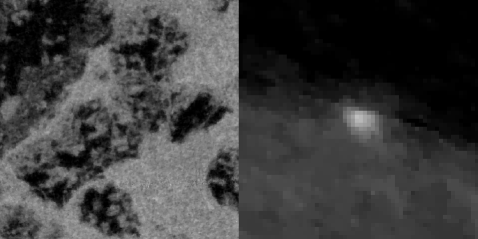

ASD-POCS (projection up-sampling)

ASD-POCS (spatial frequency constraints)

Finally, we show images for ASD-POCS using up-sampling and frequency constraints, and the resulting region-of-interest images are shown in Fig. 3. For the up-sampling method the data are up-sampled at each projection so that the data set size nominally becomes 1878 views by 9064 virtual bins prior to reconstruction by ASD-POCS. The frequency constraint ASD-POCS takes the original 18782266 data set as input. As can be seen in the figure, both approaches remove the disturbing noise pattern seen at the bottom of Fig. 2. Each of these images show some potential advantage over FBP in that the wire appears to be better focused in the up-sampling approach, and the image noise level is reduced approximately 20% for both up-sampling and frequency constrained ASD-POCS. It is possible that the frequency constraint method could lead to better resolution by allowing to be increased. Such a study will be investigated in future work.